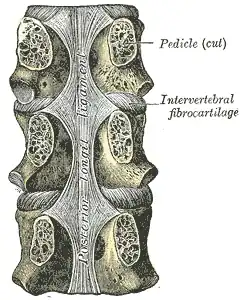

Posterior longitudinal ligament, in the thoracic region

Posterior longitudinal ligament, in the thoracic region -